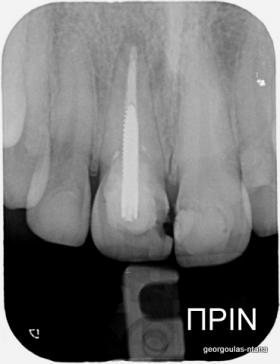

ΑΠΟΚΑΤΑΣΤΑΣΗ ΑΝΩ ΚΕΝΤΡΙΚΟΥ ΤΟΜΕΑ ΜΕ ΜΟΝΗΡΕΣ ΕΜΦΥΤΕΥΜΑ

Η κοπέλα αυτή ήρθε στο ιατρείο με κάταγμα στον δεξιό άνω κεντρικό τομέα. Το δόντι είχε απονευρωθεί στο παρελθόν και είχε αποκατασταθεί με βιδωτό άξονα κ ανασύσταση με ρητίνη και το αισθητικό αποτέλεσμα ήταν φτωχό. Η ασθενής ήθελε να είναι καλυμμένη αισθητικά για όσο χρονικό διάστημα θα διαρκούσε η θεραπεία. Πραγματοποιήθηκε τομογραφία κωνικής δέσμης (CBCT) στην περιοχή και αποφασίστηκε να γίνει εξαγωγή του δοντιού, διατήρηση του όγκου του φατνίου και 3 μήνες μετά τοποθέτηση εμφυτεύματος με ταυτόχρονη χρήση μοσχευμάτων σκληρών κ μαλακών ιστών  για βέλτιστο αισθητικό αποτέλεσμα. Το εμφύτευμα αποκαταστάθηκε με υβριδικό κολόβωμα από διπυριτικό λίθιο και ολοκεραμική στεφάνη από διπυριτικό λίθιο (Emax). Καθ’ όλη τη διάρκεια της θεραπείας, η ασθενής ήταν καλυμμένη αισθητικά με γέφυρα Meryland  συγκολλημένη στα δύο διπλανά δόντια. Μετά την οστεοενσώματωση του εμφυτεύματος και πριν την τελική αποκατάσταση, τοποθετήθηκε στο εμφύτευμα προσωρινή εργασία με σκοπό τη βελτίωση των ούλων.